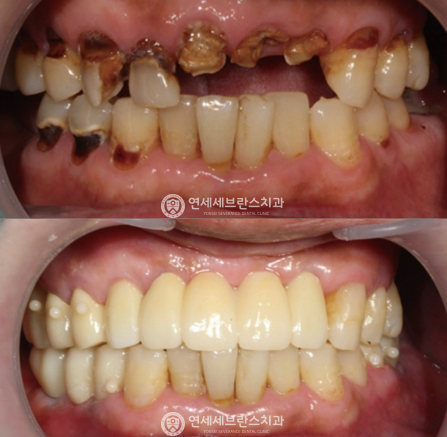

03

전악 임플란트

치아가 하나도 없거나 심각한 구강질환을 앓고 있어도

전악 보철을 제작, 임플란트를 치조골에 식립해

기능적, 심미적으로 자연치아와 가장 유사한 수준으로 재현이 가능합니다.